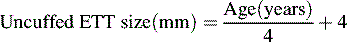

The infant upper airway is shaped like a funnel, whereas the upper airway of the older child and adult is more tubular. The glottis of an infant is located more anteriorly and more cephalad than in an older child, and the epiglottis is longer, making intubation of the trachea more difficult in the small infant, especially when the neck is hyperextended. The narrowest portion of the infant's airway is at the level of the cricoid, whereas the narrowest portion of the airway in the adult is at the level of the vocal cords. Small amounts of edema or obstruction in the cricoid (subglottic) area will produce an increase in airway resistance and can lead to respiratory failure. Postnatally the airways increase in both length and diameter and major changes occur in the terminal respiratory units as the number and size of the alveoli increase.49,182

Ventilation

The process of gas movement in and out of the lungs is defined as ventilation. Minute ventilation (volume per minute image) is the product of respiratory frequency and tidal volume:

image

For example, a patient breathing 30 times per minute, with a tidal volume of 100   mL, has a minute ventilation of 30  ×  100   mL, or 3000   mL/min.